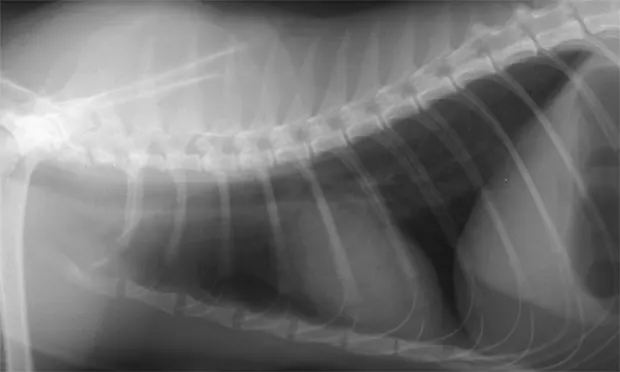

Reporting Technique for Thoracic Abnormalities